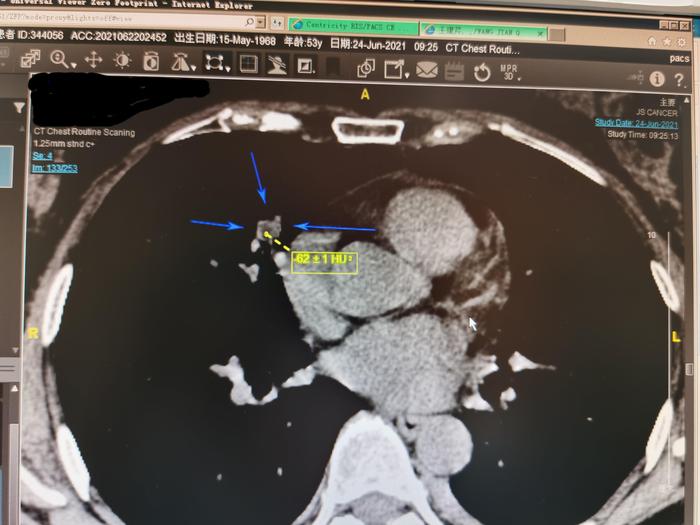

上图是我把这个结节由肺窗转变为纵隔窗。可见此结节内部局部看起来发暗。

我仔细测量其中一小块发暗的区域,CT值为-62,说明局部有脂肪密度,此实性结节内部有脂肪成分。有脂肪成分的实性肺结节一般是良性肺结节。